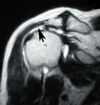

What kind of injury is this?

This is a SLAP tear (superior labrum anterior posterior)

This is an injury of the labrum of the shoulder. The labrum is a rin of fibrocartilage that surounds he edge of the articular head of a bone.